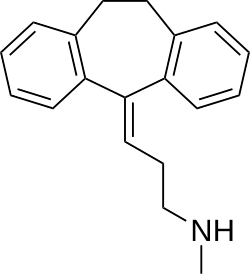

| Formula | C19H21N |

Nortriptyline is an active metabolite of amitriptyline by demethylation in the liver. Chemically, it is a secondary amine dibenzocycloheptene and pharmacologically it is classed as a first-generation antidepressant.[36]

Nortriptyline is a tricyclic compound, specifically a dibenzocycloheptadiene, and possesses three rings fused together with a side chain attached in its chemical structure.[43] Other dibenzocycloheptadiene tricyclic antidepressants include amitriptyline (N-methylnortriptyline), protriptyline, and butriptyline.[43][44] Nortriptyline is a secondary amine tricyclic antidepressant, with its N-methylated parent amitriptyline being a tertiary amine.[45][46] Other secondary amine tricyclic antidepressants include desipramine and protriptyline.[47][48] The chemical name of nortriptyline is 3-(10,11-dihydro-5H-dibenzo[a,d]cyclohepten-5-ylidene)-N-methyl-1-propanamine and its free base form has a chemical formula of C19H21N1 with a molecular weight of 263.384 g/mol.[49] The drug is used commercially mostly as the hydrochloride salt; the free base form is used rarely.[49][50] The CAS Registry Number of the free base is 72-69-5 and of the hydrochloride is 894-71-3.[49][50][51]